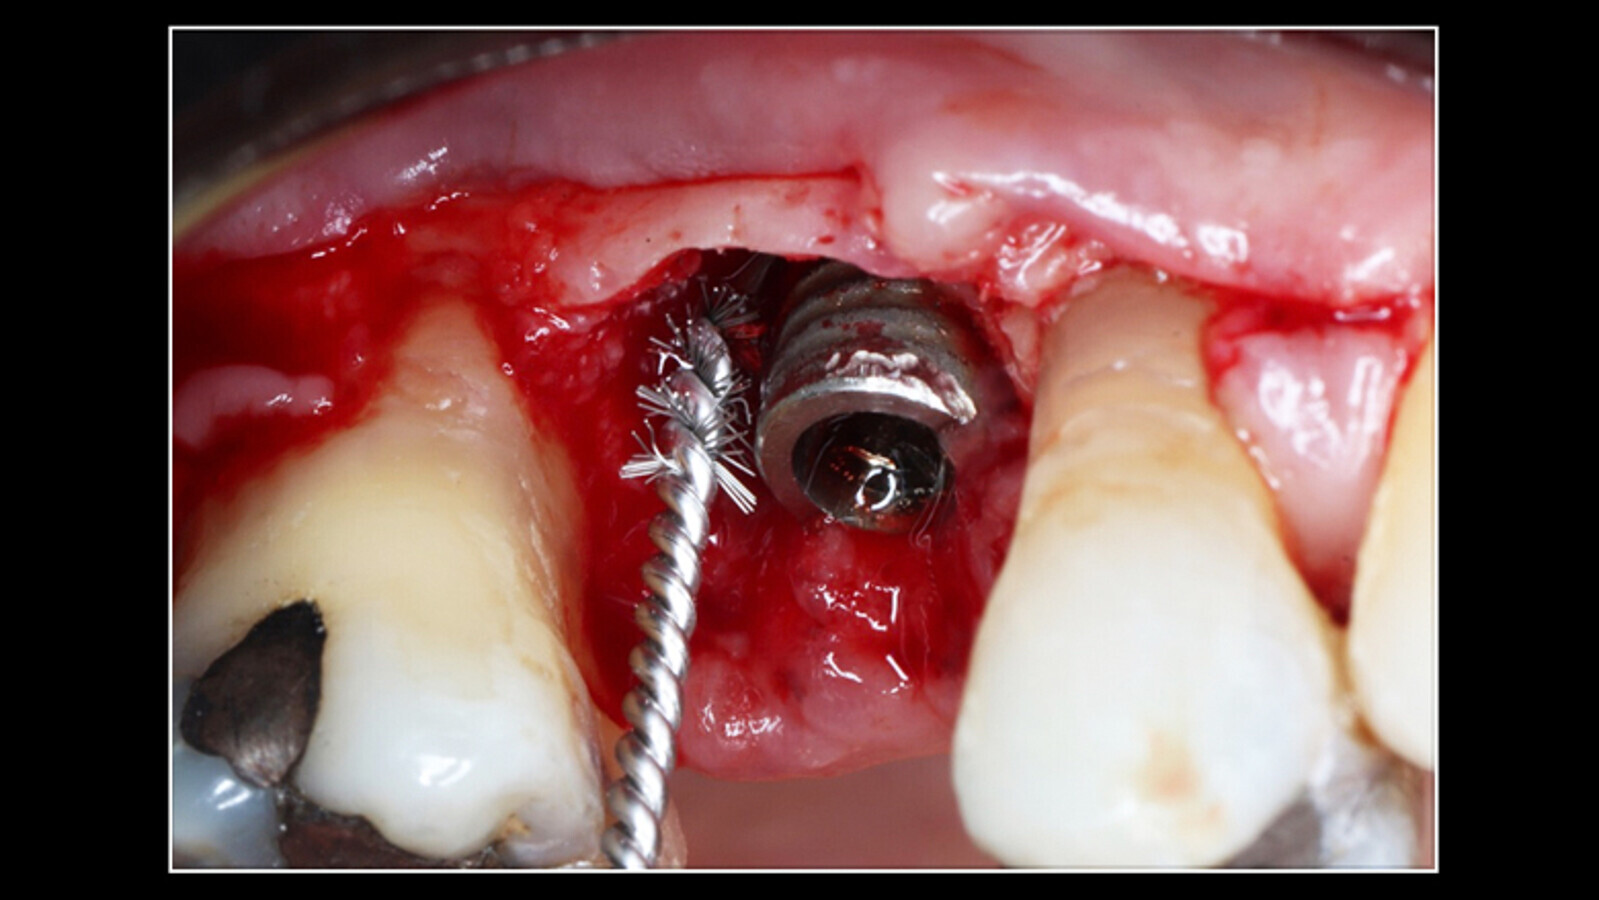

Figura 1. El examen clínico muestra enrojecimiento de la zona, presencia de sangrado, profundidad al sondaje vestibular de 8-8-8 mm y distal 8-8-8 mm. (Fotos: Samia Isaac / Ivan Herrera )

Paciente femenino de 67 años de edad, sana, no medicada. Acude a consulta por dolor en zona de segundo premolar superior derecho tratado con implante post-exodoncia, 2 años de evolución; al examen clínico se observa edema, enrojecimiento de la zona, presencia de sangrado (Figura 1), profundidad al sondaje vestibular de 8-8-8 mm y distal 8-8-8 mm.

A los 20 días de controlada la infección se realiza procedimiento quirúrgico resectivo y regenerativo, aplicación de anestésico troncular infraorbitario maxilar superior derecho con Arteek, refuerzo por palatino, posterior levantamiento de colgajo por vestibular, curetaje de todo el tejido granulomatoso alrededor del implante, aplicación de Perisolv(cloramina, Regedent, Suiza) en el defecto óseo periimplantar por 60 segundos, posterior lavado con solución salina, descontaminación del implante con cepillo de titanio Straumann (Suiza) (Figura 3).

Figura 3. Curetaje de todo el tejido granulomatoso alrededor del implante, aplicación de Perisolv en el defecto óseo periimplantar por 60 segundos, lavado con solución salina y descontaminación del implante con cepillo de titanio.